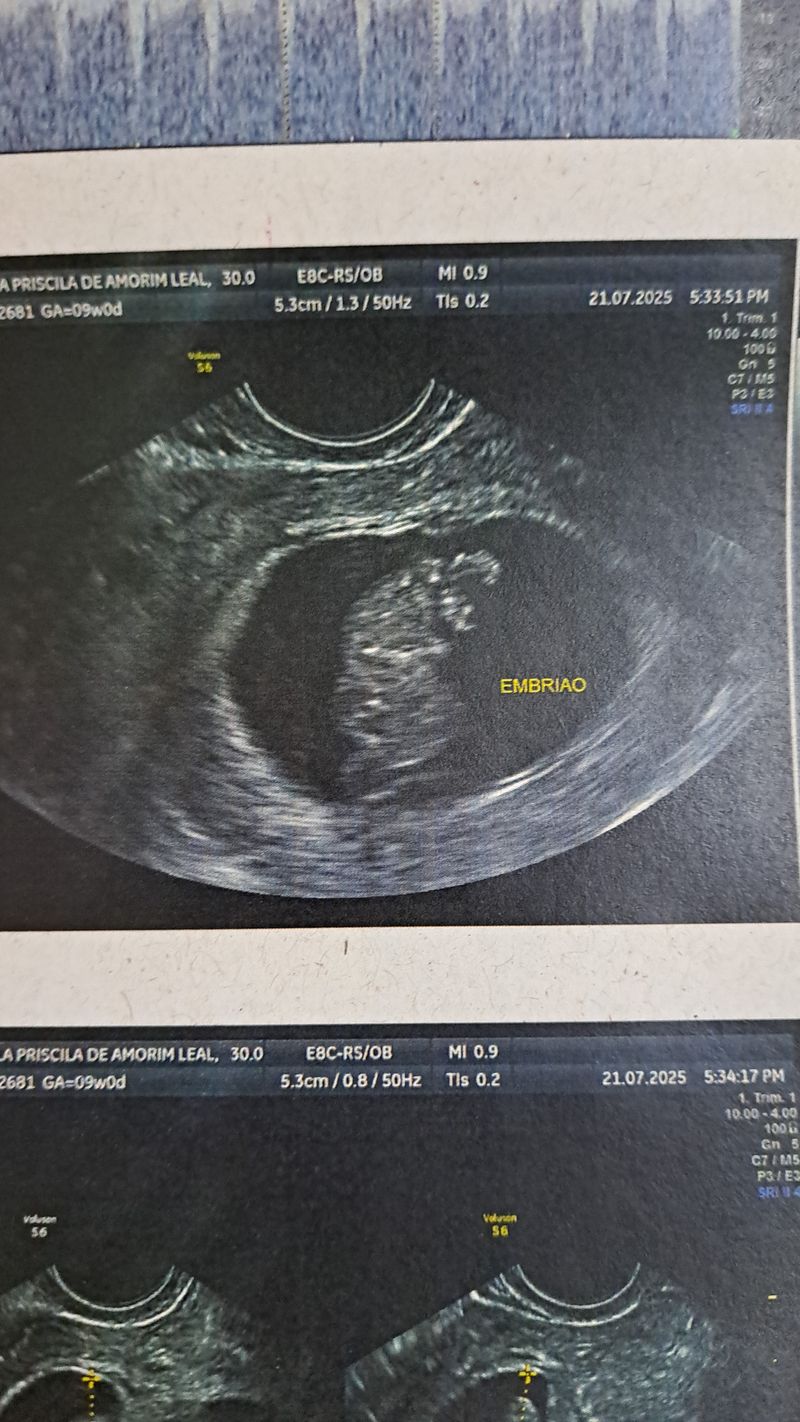

Minhas primeiras fotinhas

Eu ainda estou no forminho, mas a mamãe já tem várias fotos e vídeos, confere aí em baixo meu pessoal! 👶